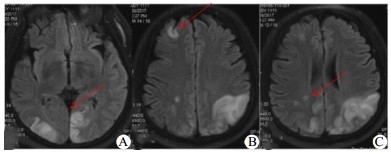

2 结果根据MRI显示的病灶部位,发现失血性休克导致的脑梗死,梗死灶多数在双侧的分水岭区,少数呈点状散乱分布(图 1)。根据Bogousslavsky[3]对脑分水岭梗死的分型:皮质前型、皮质后型、皮质下型。多数患者为皮质后型,其次为皮质下型,再者为皮质前型。参照牛津郡社区脑卒中项目(OCSP)分型标准[4]进行分组:前循环梗死、后循环梗死、全循环梗死。对比观察梗死灶在首次、1个月、2个月、3个月后在MRI上的变化。入院时,前循环梗死28例(73.6%),后循环梗死33例(86.8%), 全循环23例(60.5%)。1个月时,27例梗死灶明显缩小伴部分梗死灶影像上消失,11例梗死灶部分缩小伴部分梗死灶影像上消失。2个月时,26例遗留小的陈旧性腔梗,其中前循环18例,后循环23例,全循环15例。3个月时和2个月时比较,没有明显变化。

| A、B、C为同一患者多层面的图像,患者,男性,50岁,多发伤致失血性休克,入院时昏迷状态,脉搏、血压测不到,紧急手术输血、输液,1 d后恢复意识,诉视物模糊,MRI示多发性脑梗死 图 1 患者头部MRI检查结果 |